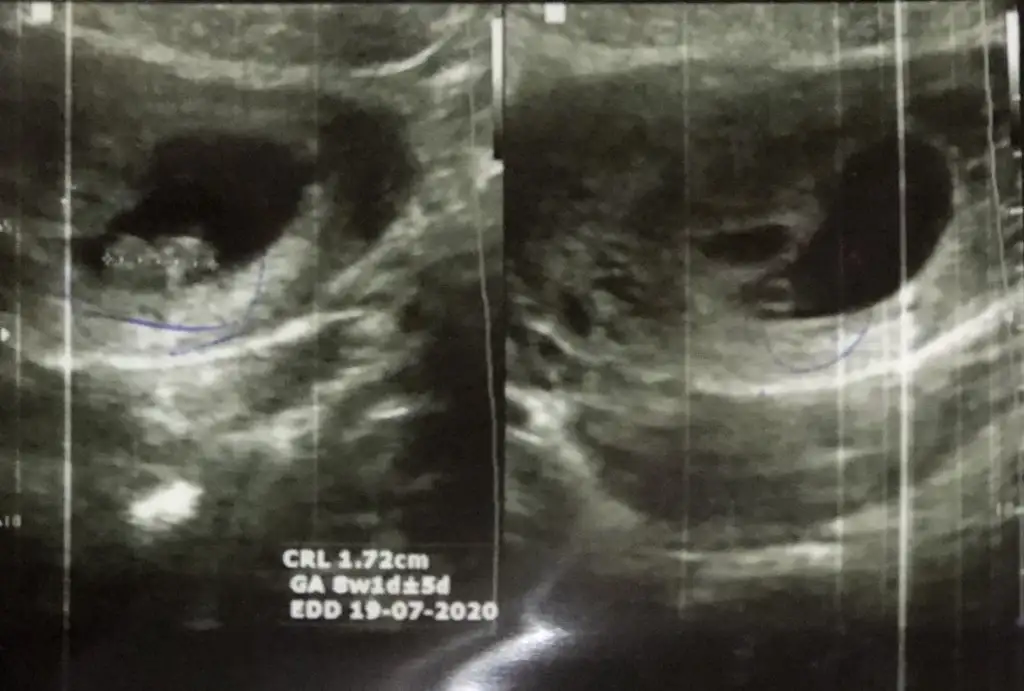

Keseye göre karından bakıldıysa erkekGerçekten miii☺☺ Bir de 8. Hafta ve 6. Hafta var. Kaybolan ikiz sendromu yaşadığım için doktor 1 ay sonra gelin demişti. O yüzden 12. Hafta var.onları da ekleyeyim.

Buna göre kız sanki ama 11 +yada 12+ usg de paylaşın değişebilir nubu bu haftalarda iki tarafa benzerMerhabaIkra meyra ben de merak ediyorum 10haftalık görüntüsü bu acaba bakabilir misiniz?

Daha önce aynı usg paylaştınız nubu net değil sanki erkek demiştimKizlar benimkine dd bakar misinizizzzz